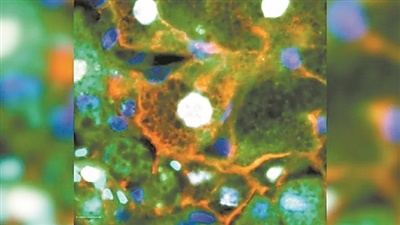

显微镜图像显示,“领导细胞”会快速迁移到伤口边缘,其中“领导细胞”的细胞核呈白色,细胞膜呈红色。图片来源:美国趣味科学网站

研究小组还观察了小鼠体内“领导细胞”如何修复乙酰氨基酚导致的肝损伤。他们注意到,在伤口愈合过程中,这些细胞一马当先,迅速闭合伤口,然后细胞快速增殖,进一步密封伤口。这表明,在制造新组织前,肝脏优先考虑闭合伤口,防止细菌进入器官引起广泛感染。